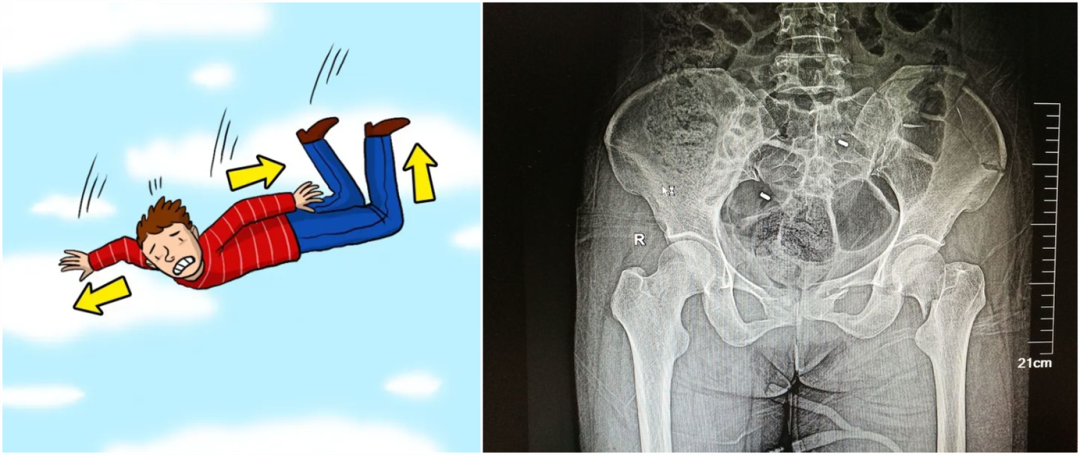

從暴力的大小來看,還可以細分為高能量的損傷和低能量的損傷。比如說,如果是車子撞的,從高處墜落,通常會造成高能量的損傷,而普通的跌倒造成的骨折,一般不太嚴重,可以說是低能量的損傷。

我們通常會把骨盆骨折分為外傷性的骨折(也就是暴力性的骨折)和病理性的骨折。暴力性骨折多是由外傷引起的,病理性的骨折有可能是病人患有某些疾病,比如腫瘤、骨質疏松等引起的一些在外力較小的情況下發生的骨折,這叫“病理性的骨折”。

外傷性骨折